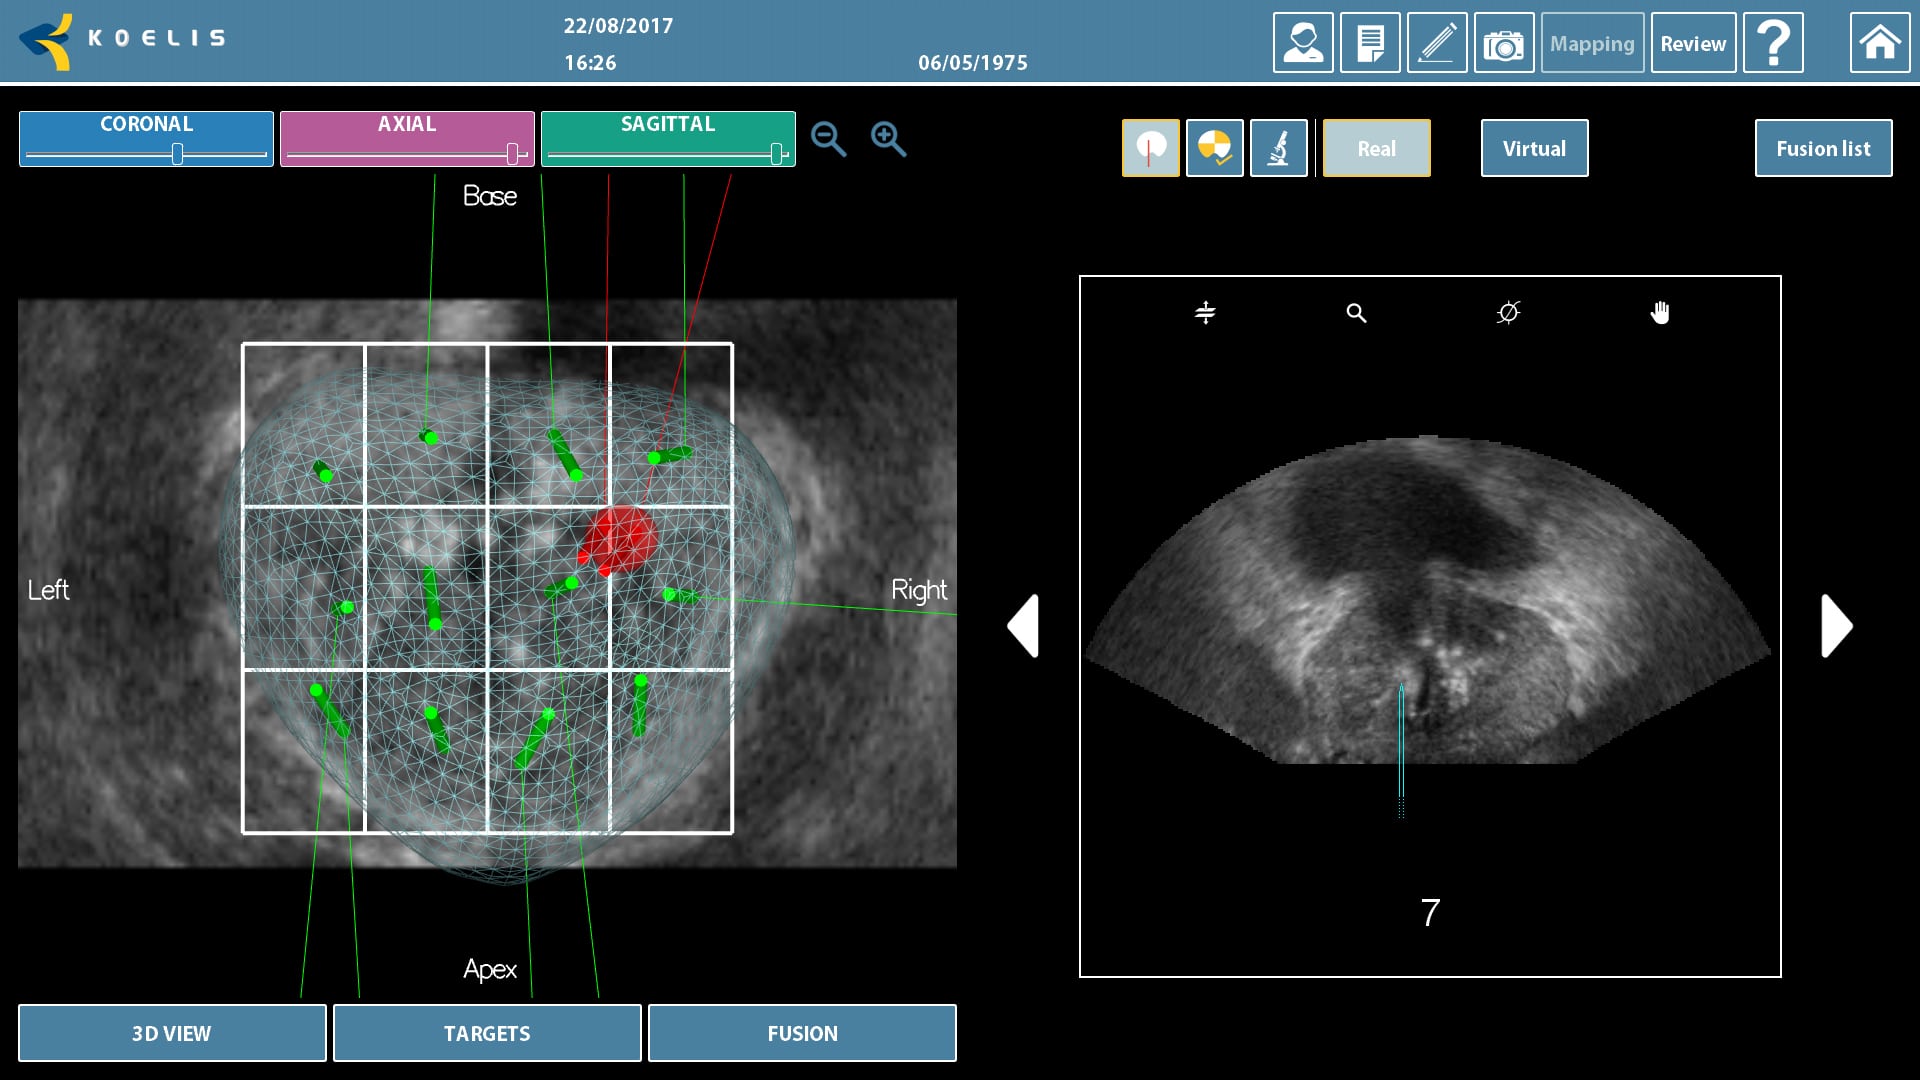

En aquells casos en què la ressonància magnètica mostri l’existència d’àrees sospitoses de correspondre a un càncer de pròstata s’ofereix la possibilitat de realitzar una biòpsia mitjançant fusió. En la fusió s’utilitza un sistema informàtic que combina les imatges extretes de la ressonància magnètica multiparamètrica amb les obtingudes en directe amb l’ecografia. El sistema informàtic (programari de fusió) genera una imatge 3D de la pròstata molt exacta en què es pot localitzar amb precisió en l’ecografia les lesions sospitoses visualitzades en la ressonància magnètica. Aquest sistema actua com un GPS de gran precisió dins de la pròstata. Aquest sistema millora la probabilitat de detectar tumors de pròstata sobretot si les lesions tumorals són petites o la pròstata és voluminosa.